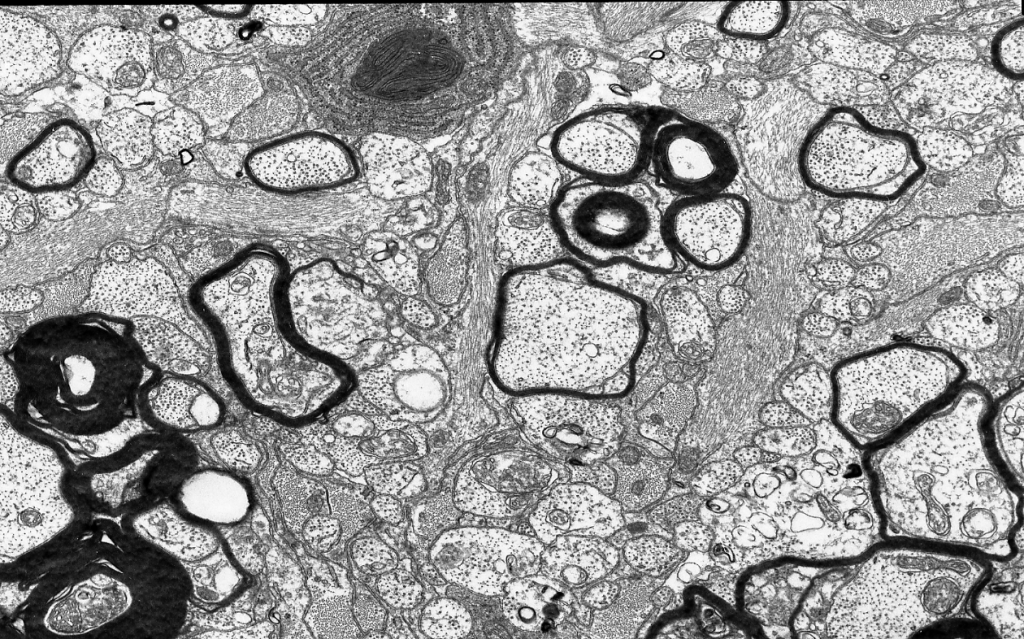

The Axo-Glial Research Group studies the functions of the cells that form myelinated axons in the central nervous system. Myelinated axons are injured in multiple sclerosis (MS), stroke, Alzheimer’s disease, motor neuron disease and several other neurodegenerative conditions. We aim to understand why myelinated axons are so susceptible and how we might protect them. The 3D model of the cytosolic channels of myelin was generated by Eleanor McGowan from an image of a tdTomato labelled myelinating oligodendrocyte captured by Julia Edgar.